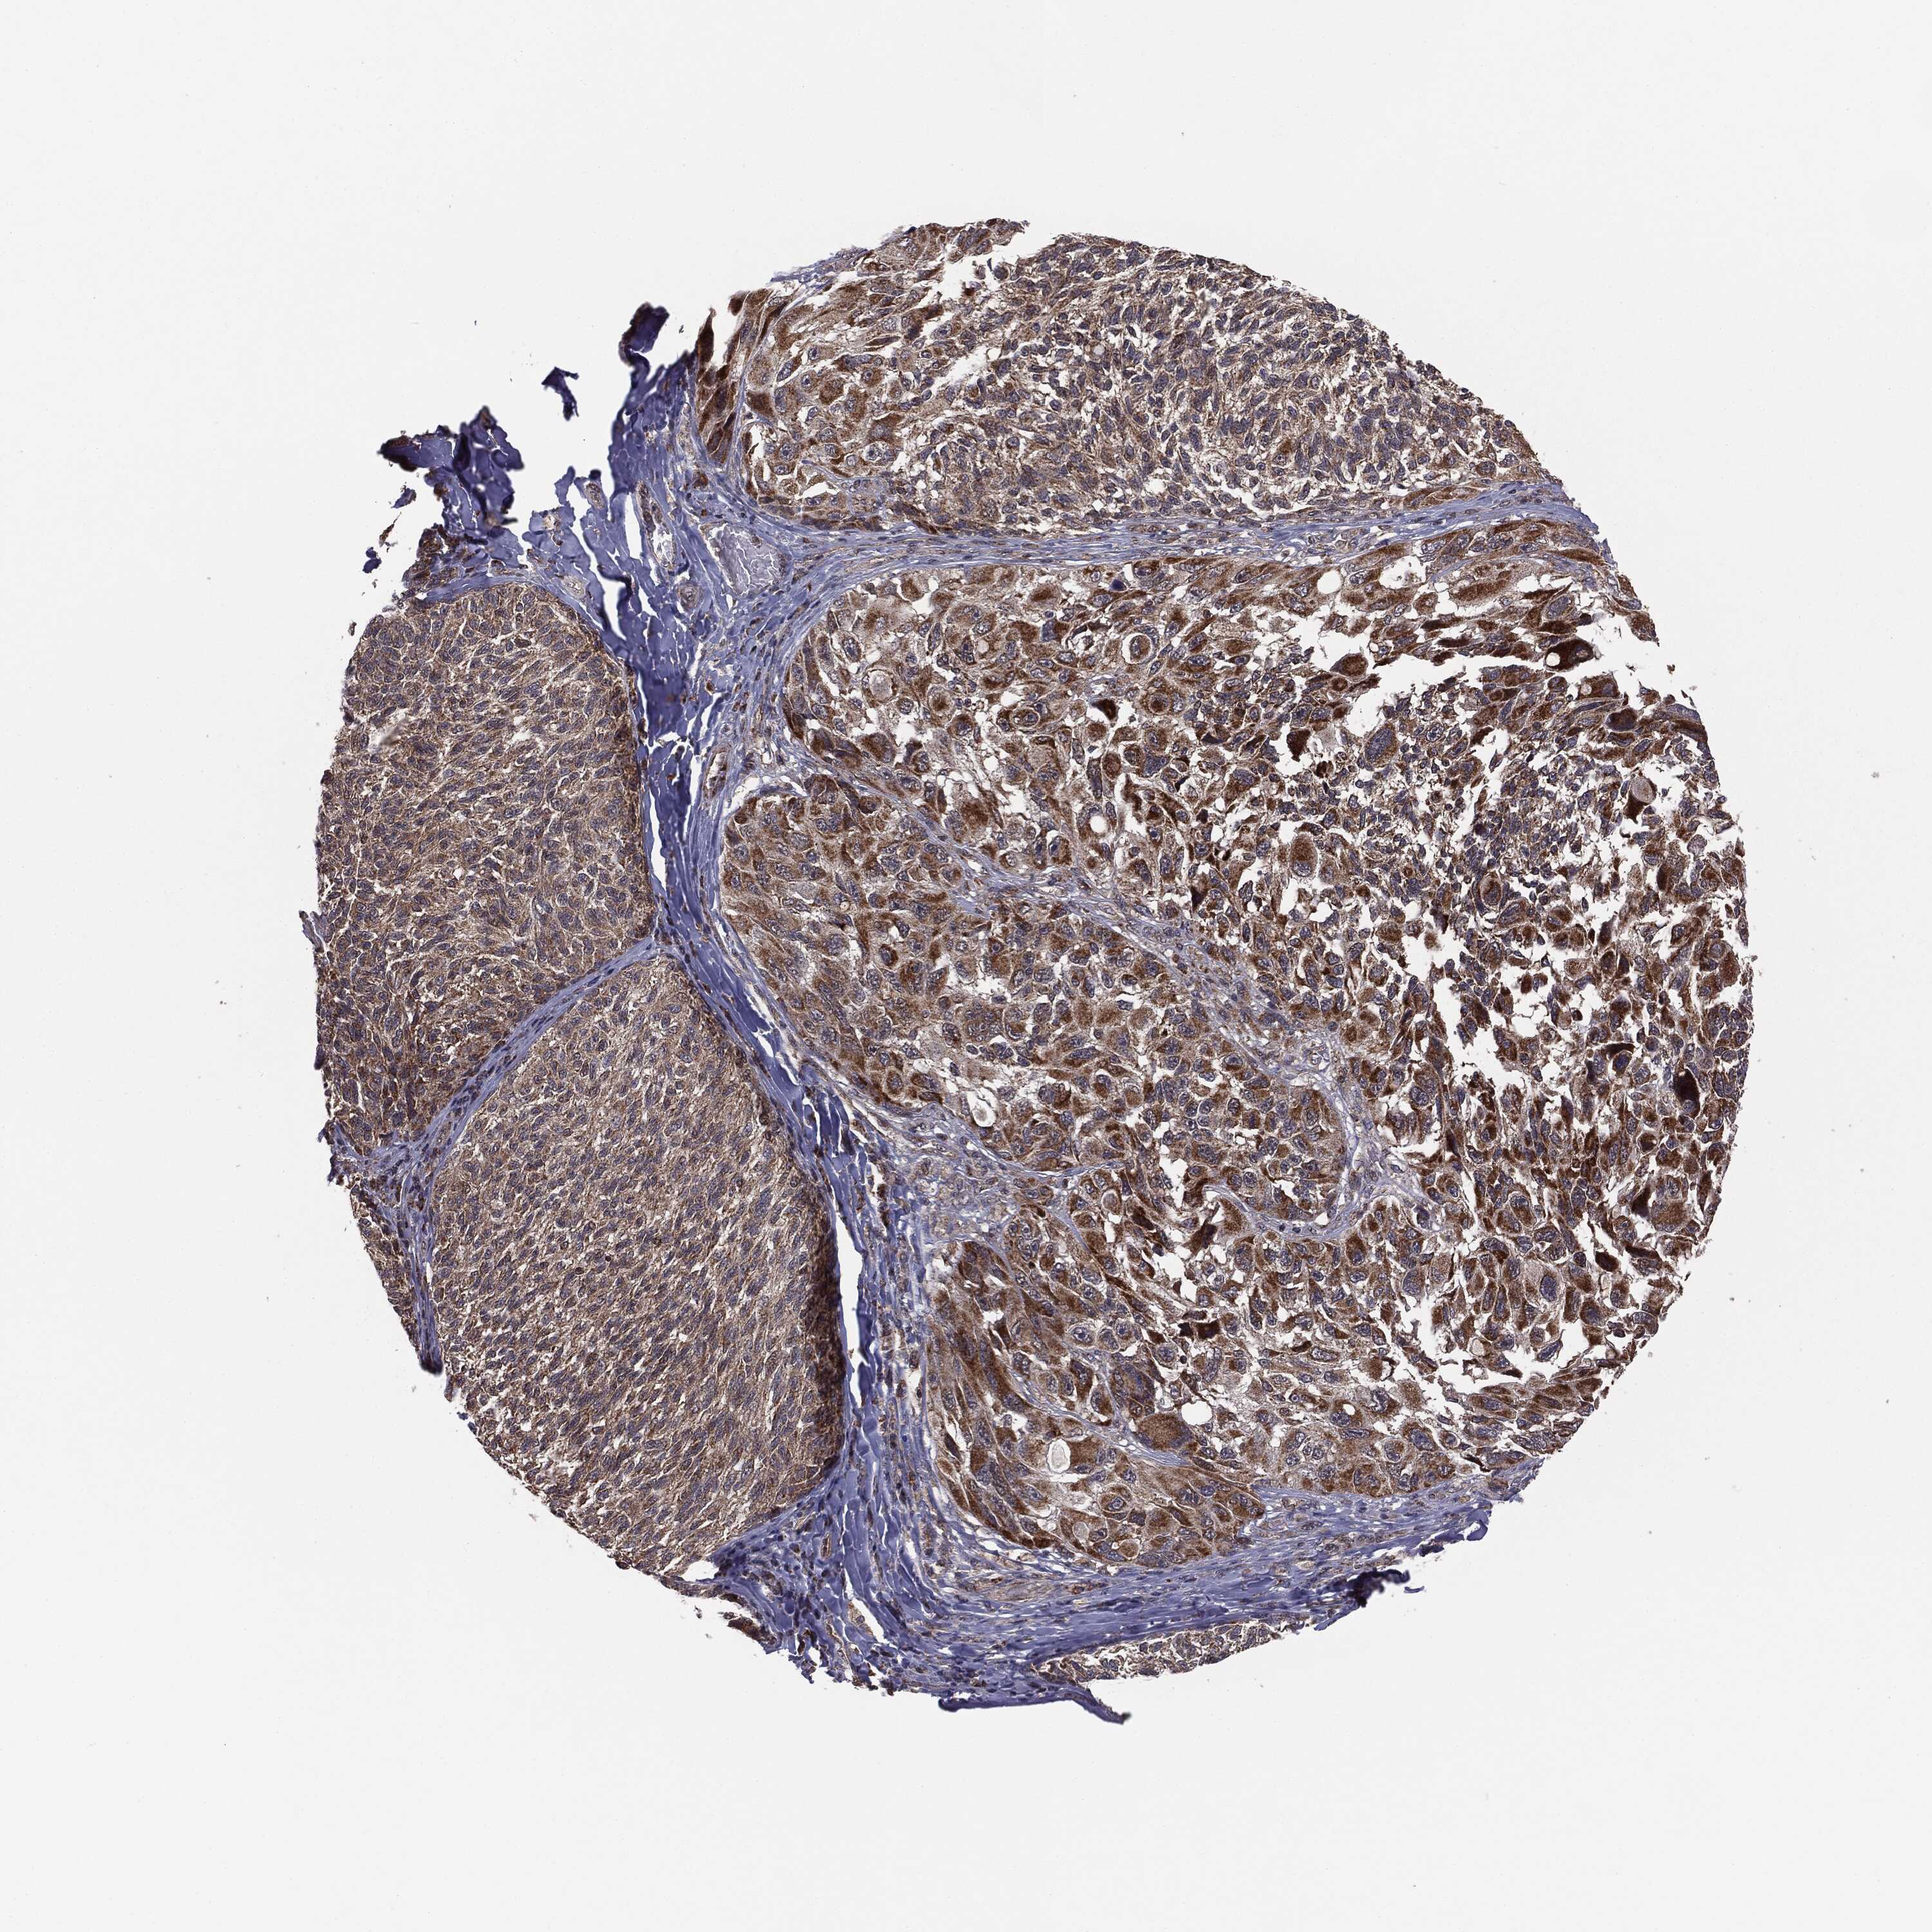

MELANOMA - Protein expressioni

A mouse-over function shows sample information and annotation data. Click on an image to view it in a full screen mode. Samples can be filtered based on level of antibody staining by selecting one or several of the following categories: high, medium, low and not detected. The assay and annotation is described here.

Note that samples used for immunohistochemistry by the Human Protein Atlas do not correspond to samples in the TCGA dataset.

Antibody stainingi

Antibody staining in the annotated cell types in the current human tissue is reported as not detected, low, medium, or high, based on conventional immunohistochemistry profiling in selected tissues. This score is based on the combination of the staining intensity and fraction of stained cells.

Each image is clickable and will lead to virtual microscopy that enables deeper exploration of all samples and also displays staining intensity scores, fraction scores and subcellular localization as well as patient and tissue information for each sample.

Malignant melanoma, NOS

Malignant melanoma, Metastatic site